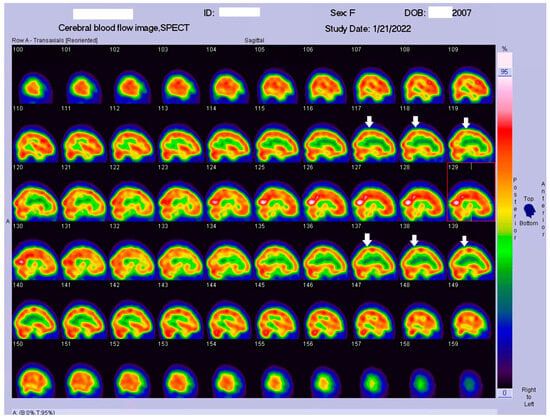

HSAN4 is a rare genetic disorder with a complex clinical presentation. Our hypothesis that the CNS might be implicated in this condition gained substantial support from the clinical manifestations observed in our patient. The presence of spasticity in her feet and a strong positive Babinski’s sign, which are characteristics commonly found in patients with upper motor neuron (UMN) lesions [16], prompted us to explore the potential involvement of the central nervous system (CNS) in HSAN4. To investigate this novel aspect, we employed Tc−99m ECD SPECT imaging for assessing cerebral blood flow and revealing perfusion deficits within the brain [23]. This study represents the pioneering visualization of brain perfusion abnormality in an HSAN4 patient, and the findings are nothing short of groundbreaking. Our Tc−99m ECD SPECT imaging revealed multiple areas within the CNS with perfusion deficits. Notably, these deficits were observed in the cerebellum (Figure 2), thalamus (Figure 3), and postcentral gyrus of the parietal lobe (Figure 4 and Figure 5). These findings suggest that HSAN4 has the potential to affect not only the peripheral nervous system (PNS) but also the CNS, ushering in a new era in our understanding of this complex disorder. One of the most significant and intriguing aspects of our findings is the localization of these deficits in the postcentral gyrus and thalamus. These regions play pivotal roles in processing pain signals transmitted from the spinothalamic and spinoreticular tracts [24]. The spinothalamic and spinoreticular tracts are the central pathway for nociceptive signals, conveying pain information from the peripheral nervous system to the cerebral cortex. The former pathway originates from the dorsal root ganglia, traverses the dorsal horn of the spinal gray matter, proceeds to the ventral posterolateral nucleus of the thalamus, and finally reaches the posterior limb of the internal capsule. The latter tract also handles nociceptive signals, routing them to the thalamus and postcentral gyrus [25,26]. The perfusion deficits we observed in these crucial pain-processing areas offer a profound and novel perspective on explaining the pain insensitivity characteristic of HSAN4 patients. While previous research has primarily focused on the peripheral mechanisms of pain insensitivity, our study provides compelling evidence that the origin of this phenomenon might extend beyond the peripheral nervous system.

In essence, pain insensitivity in HSAN4 involves intricate CNS mechanisms. The perfusion deficits in the thalamus and postcentral gyrus shed light on how HSAN4 may disrupt these critical pathways, leading to the observed pain insensitivity. This revelation challenges conventional thinking and highlights the importance of considering both peripheral and central components in our understanding of HSAN4.

Figure 4. Coronal view of the Tc−99m ECD brain perfusion SPECT images. A decreased uptake in the tracer can be observed in the parietal area, especially in the postcentral gyrus (arrow).

Figure 5. Sagittal view of the Tc−99m ECD brain perfusion SPECT images. A decreased uptake in the tracer can be observed in the parietal area, especially in the postcentral gyrus (arrow).